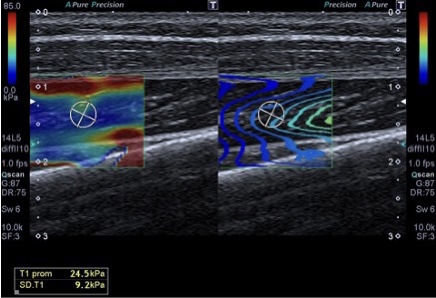

357. Kilopascales (kPc) en Elastrografía. Lo que el TSID debe saber.

Cuando hablamos de medicina moderna, las tecnologías de imagen han revolucionado la forma en que diagnosticamos y tratamos una variedad de enfermedades. Entre estas tecnologías se encuentra la elastografía, un método no invasivo para evaluar la rigidez de los tejidos internos del cuerpo. Pero, ¿alguna vez te has preguntado cómo se mide esta rigidez? Aquí es donde entran en juego los kilopascales (kPa). En este post, exploraremos qué son los kilopascales, su importancia en la elastografía y cómo se utilizan en la práctica médica.

La Importancia de los Kilopascales en Elastografía

La elastografía es una técnica que mide la rigidez o elasticidad de los tejidos blandos, como el hígado, los músculos y otros órganos. Esta técnica es especialmente valiosa para detectar cambios en la rigidez del tejido que podrían indicar condiciones médicas como fibrosis, cirrosis o tumores. En el ámbito de la elastografía, las medidas de rigidez se expresan típicamente en kilopascales.

• Evaluación Musculoesquelética: Utilizado en ortopedia para evaluar la rigidez de músculos y tendones.

Valores Normales de Rigidez

En el Tejido Hepático

• Normal: Entre 4,0 y 5,8 kPa.

• Fibrosis leve: Entre 6 y 7 kPa.

• Fibrosis moderada: Entre 8 y 9 kPa.

• Cirrosis: Más de 12-14 kPa.

En Tejidos Musculares Principales

La rigidez de los músculos puede variar, pero generalmente son más duros (mayor rigidez medida en kPa) cuando están contraídos y más blandos cuando están relajados.